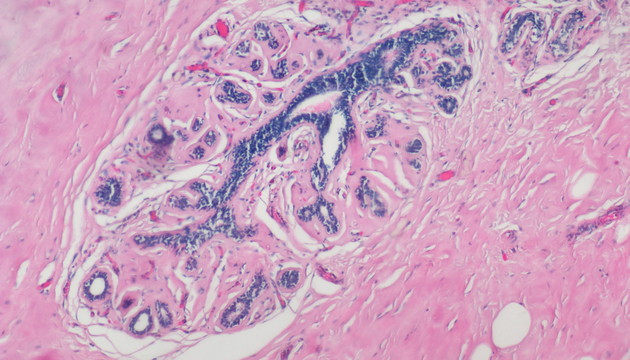

依據(jù)癌細胞在分子表達層面和細胞組織層面的變化,運用各類顯微成像技術對癌細胞進行篩選與識別,如①病理切片②免疫組化(IHC)③原位熒光雜交(FISH)④循環(huán)腫瘤檢測(CTC)⑤腫瘤細胞培養(yǎng)研究

癌癥研究中的成像有明場和熒光兩類,明場設備要求低,但病理切片全片判讀工作量大,效率低,使用切片掃描系統(tǒng)通過電動掃描和拼接軟件,實現(xiàn)高效全局成像與局部放大,可提升診斷精度與效率;多色熒光成像高靈敏度、高特異性,但信號弱,需優(yōu)化激發(fā)光、濾光片、成像設備及圖像處理,以獲取清晰多通道信號;對于細胞培養(yǎng),還有如何長時間成像監(jiān)測,同時減少污染、不影響細胞生長的困難

(1)全能型設備:明美數(shù)字切片掃描系統(tǒng)MDS4+MSX2/MS60,融合切片掃描功能與研究級熒光顯微鏡,適用于病理切片、CTC、FISH、IHC等多種檢測。 (2)FISH、CTC、IHC專用:MF43-N/MF53-N+MS23/MSX11,搭配FISH軟件,支持多色熒光通道,高靈敏度成像,智能優(yōu)化圖像。 (3)癌細胞培養(yǎng)觀測:活細胞成像儀MCS11/MCS21/MCS22+電腦,培養(yǎng)箱內使用,無線連接遠程管理,減少污染風險,集成多種成像模式,滿足多樣細胞培養(yǎng)觀測需求。